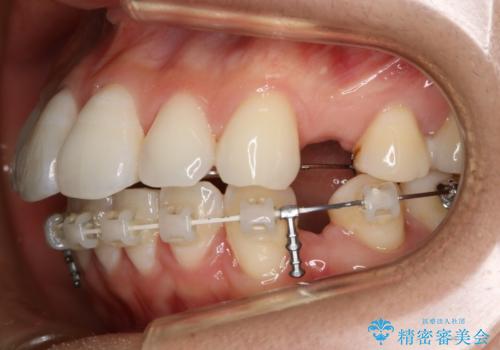

- ワイヤー(片顎舌側装置)

ハーフリンガル装置

ハーフリンガルとは上顎を裏側、下顎を表側のワイヤー装置で治療する場合をいいます。

フルリンガル(上下とも裏側)で治療するよりも費用が抑えられ、治療期間も伸びにくい傾向にあります。また、下顎の舌側に装置がないおかげで口内炎や発音障害もフルリンガルに比べて少ないとされています。